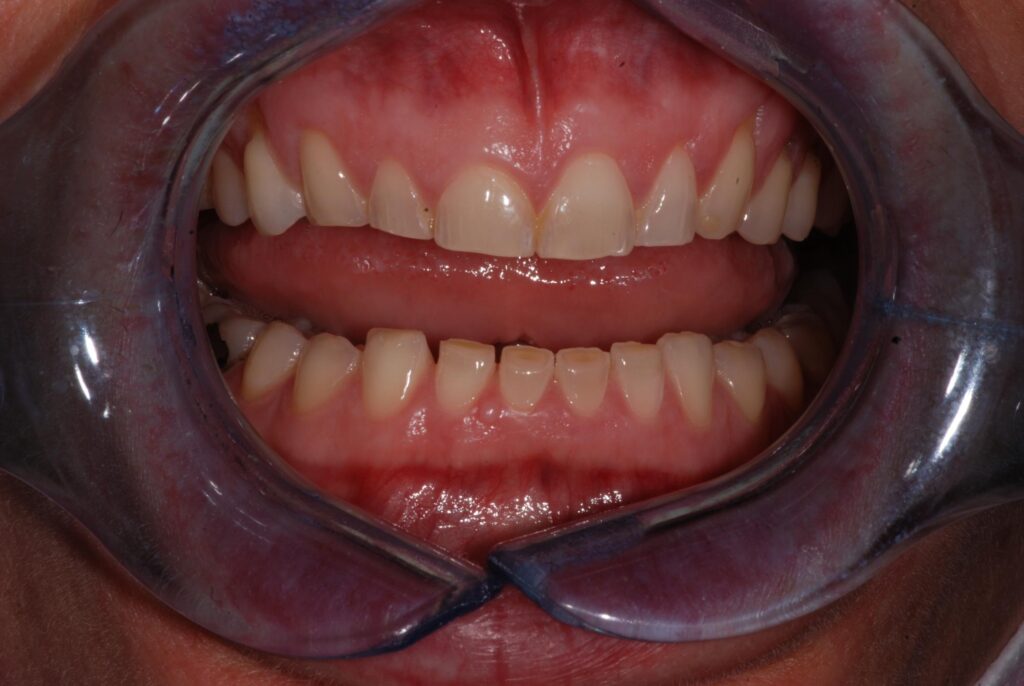

• Usura dentale visibile

Nei casi più gravi, se trascurato per anni, il bruxismo può provocare usure dentali profonde, fratture dei denti e compromissione dell’occlusione, rendendo necessari trattamenti complessi come corone multiple, ricostruzioni protesiche o riabilitazioni complete del sorriso.

• Esame clinico: controllo dell’usura dentale, della tensione muscolare e dei rumori articolari